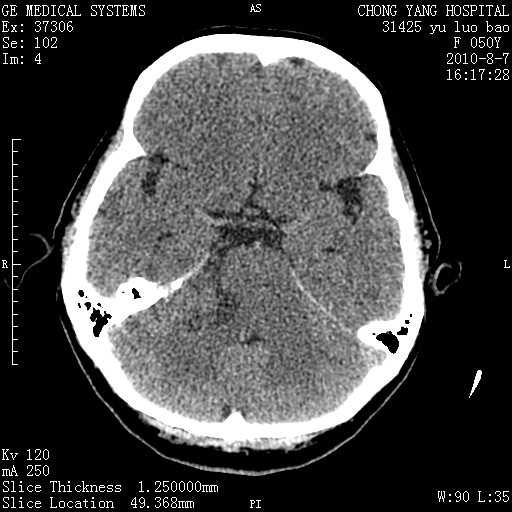

右侧桥小脑角区占位--听神经瘤,建议增强或mri检查。

右侧桥小脑角去等密度占位,右侧内听道扩大、骨质吸收,考虑:右侧听神经瘤,建议增强检查。

考虑听神经瘤可能性大。

右侧内听道扩大、骨质吸收,中脑受压左移,考虑:右侧听神经瘤,建议增强检查。支持!

右侧桥小脑角区等密度占位,内耳道扩大,听神经瘤